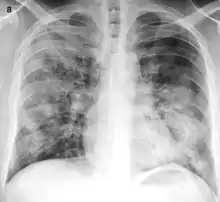

Bronchopneumonia is a subtype of pneumonia. It is the acute inflammation of the bronchi, accompanied by inflamed patches in the nearby lobules of the lungs.[1]

It is often contrasted with lobar pneumonia; but, in clinical practice, the types are difficult to apply, as the patterns usually overlap.[2] Bronchopneumonia (lobular) often leads to lobar pneumonia as the infection progresses. The same organism may cause one type of pneumonia in one patient, and another in a different patient.

On gross pathology there are typically multiple foci of consolidation present in the basal lobes of the human lung, often bilateral. These lesions are 2–4 cm in diameter, grey-yellow, dry, often centered on a bronchiole, poorly delimited, and with the tendency to confluence, especially in children.

Light microscopy typically shows neutrophils in bronchi, bronchioles and adjacent alveolar spaces.[2]